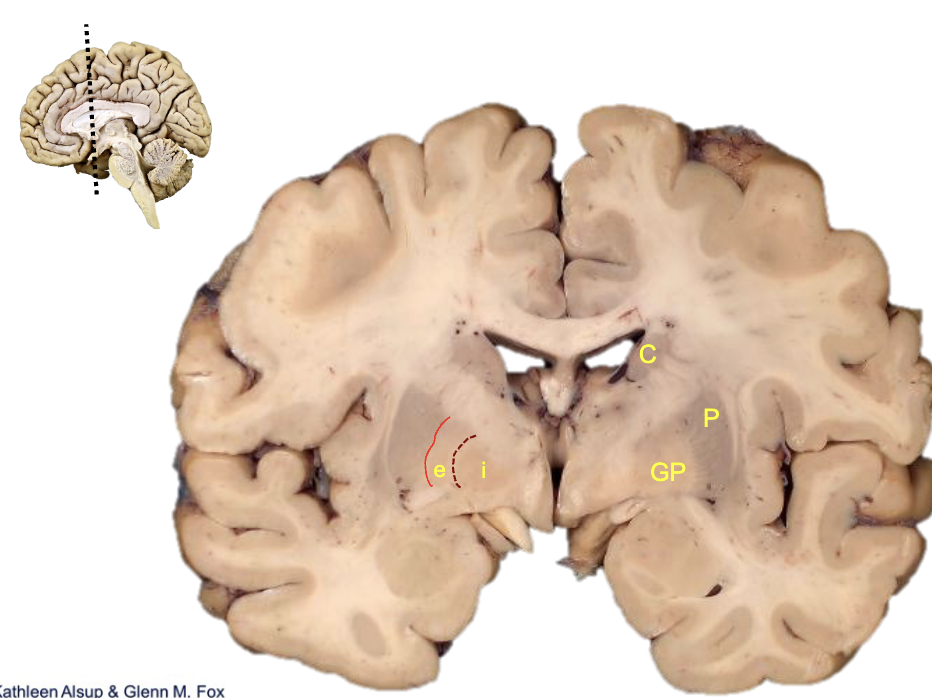

<p><strong>what is c?</strong></p>

caudate

<p><strong>what is p?</strong></p>

putamen

<p><strong>what is gp?</strong></p>

globus pallidus

<p><strong>what is i?</strong></p>

internal segment

<p><strong>what is e?</strong></p>

external segment